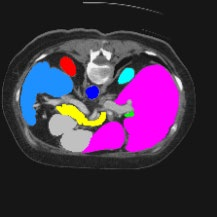

Transformers have made remarkable progress towards modeling long-range dependencies within the medical image analysis domain. However, current transformer-based models suffer from several disadvantages: (1) existing methods fail to capture the important features of the images due to the naive tokenization scheme; (2) the models suffer from information loss because they only consider single-scale feature representations; and (3) the segmentation label maps generated by the models are not accurate enough without considering rich semantic contexts and anatomical textures. In this work, we present CASTformer, a novel type of generative adversarial transformers, for 2D medical image segmentation. First, we take advantage of the pyramid structure to construct multi-scale representations and handle multi-scale variations. We then design a novel class-aware transformer module to better learn the discriminative regions of objects with semantic structures. Lastly, we utilize an adversarial training strategy that boosts segmentation accuracy and correspondingly allows a transformer-based discriminator to capture high-level semantically correlated contents and low-level anatomical features. Our experiments demonstrate that CASTformer dramatically outperforms previous state-of-the-art transformer-based approaches on three benchmarks, obtaining 2.54%-5.88% absolute improvements in Dice over previous models. Further qualitative experiments provide a more detailed picture of the model's inner workings, shed light on the challenges in improved transparency, and demonstrate that transfer learning can greatly improve performance and reduce the size of medical image datasets in training, making CASTformer a strong starting point for downstream medical image analysis tasks.